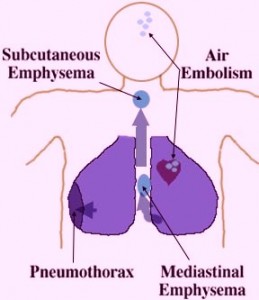

Subcutaneous emphysema or sometimes called tissue emphysema is a condition in which air or gas builds up within the skin tissues. This usually occurs when the air escapes from the airways or the lungs through a puncture or a tear. This condition is not really physically painful and patients might only feel uneven lumps and hear crackling sounds especially when these lumps are pressed together. However, complications may arise which can lead to serious life threatening situations due to air blockage or air restrictions.

Subcutaneous Emphysema Pictures

Here are photos of Subcutaneous Emphysema to know how the disease affects the body and its functioning.